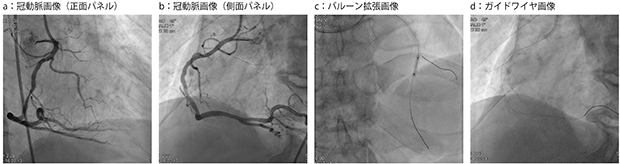

アンギオ臨床画像例:冠動脈インターベンションにおけるAlluraClarityの画像例

心臓血管センターでは,AlluraClarityファミリーの被ばく低減について評価を行い,論文で発表している。中村所長らは,“Heart and Vessels”に2015年4月に発表した“Patient radiation dose reduction using an X-ray imaging noise reduction technology for cardiac angiography and intervention”において,AlluraClarityファミリーによる冠動脈インターベンションで約66%の被ばく低減が可能であったと報告した。中村所長は,「AlluraClarityファミリーに更新したことで,従来と比較し,手技スタイルを変えることなく6割以上の被ばく低減が可能となりました。最近では,透視撮影のフレームレートを7.5fpsに落としてさらなる被ばく低減を進めています。残像がなく高画質なので,ストレスを感じることなく手技に集中できます。ほとんどの手技は透視画像を見ながら行うので,透視画像の画質は重要です。その点,AlluraClarityファミリーは低被ばくと高画質のバランスがとれており,高く評価しています」と述べる(アンギオ臨床画像例を参照)。